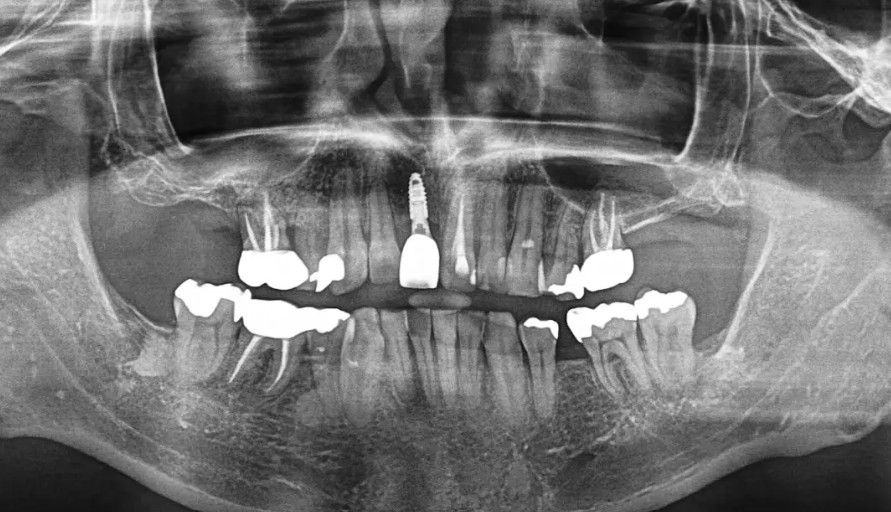

画像所見

CTで骨の高さ・厚みともに良好。頬側骨の吸収は軽度で、追加の骨移植は不要。

CTで骨の高さ・厚みともに良好。頬側骨の吸収は軽度で、追加の骨移植は不要。鼻腔底との距離も十分にあり、即時埋入が適応。

歯肉厚み(バイオタイプ)は中程度で、軟組織のボリュームも保たれていました。

→ 審美領域における即時埋入・即日仮歯装着の適応条件を満たしていると判断。

診断名:上顎右中切歯破折(保存不可能)治療計画:抜歯即時インプラント埋入